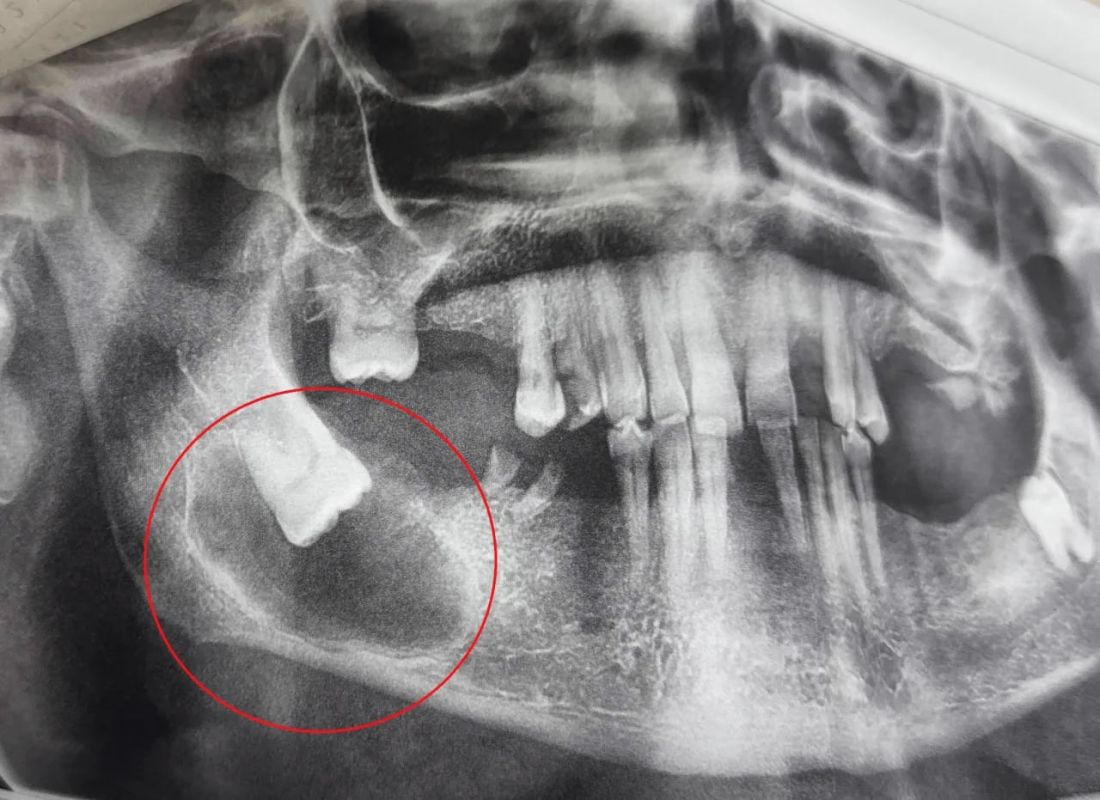

Специалисты обнаружили у пациента серьёзную проблему — непрорезавшийся зуб мудрости, расположенный горизонтально, окружённый крупной доброкачественной опухолью. Обследование показало наличие плотной круглой зоны снижения плотности костей. Зуб мудрости не смог самостоятельно прорезаться, остался внутри десны и вызвал образование опасной кисты, которая могла разрушить челюсть.

Хирурги-стоматологи провели сложную операцию под местным обезболиванием. Они аккуратно вскрыли область над зубом мудрости, удалили сам зуб и оболочку образовавшейся кисты вместе с патологическими тканями. Операцию выполнила врач Анастасия Асеева.